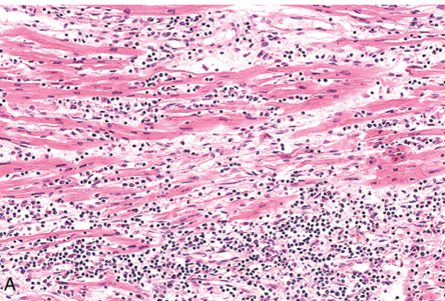

Chronic, hypersensitivity myocarditis

Multinucleate giant cells